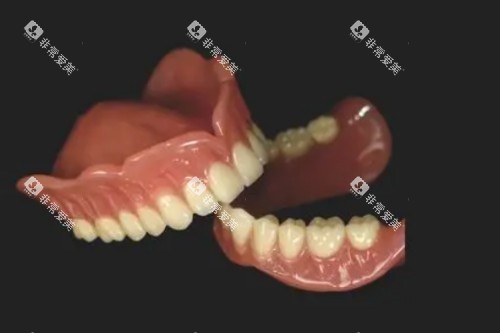

高端型吸附性义齿是目前市场上档次更高的产品,采用新型的材料和制作工艺。其基托可能使用高强度树脂、钛合金或陶瓷等材料,牙冠则多为全瓷材料。这种义齿不仅具有极强的吸附力和稳定性,还能根据患者的个性化需求进行定制。

材料:高强度树脂、钛合金、全瓷材料。

舒适度:较好,几乎无异物感。